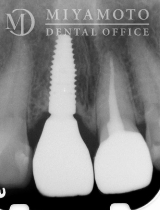

症例1

右上中切歯部インプラント及び左上中切歯部オールセラミッククラウン

同部位エックス線